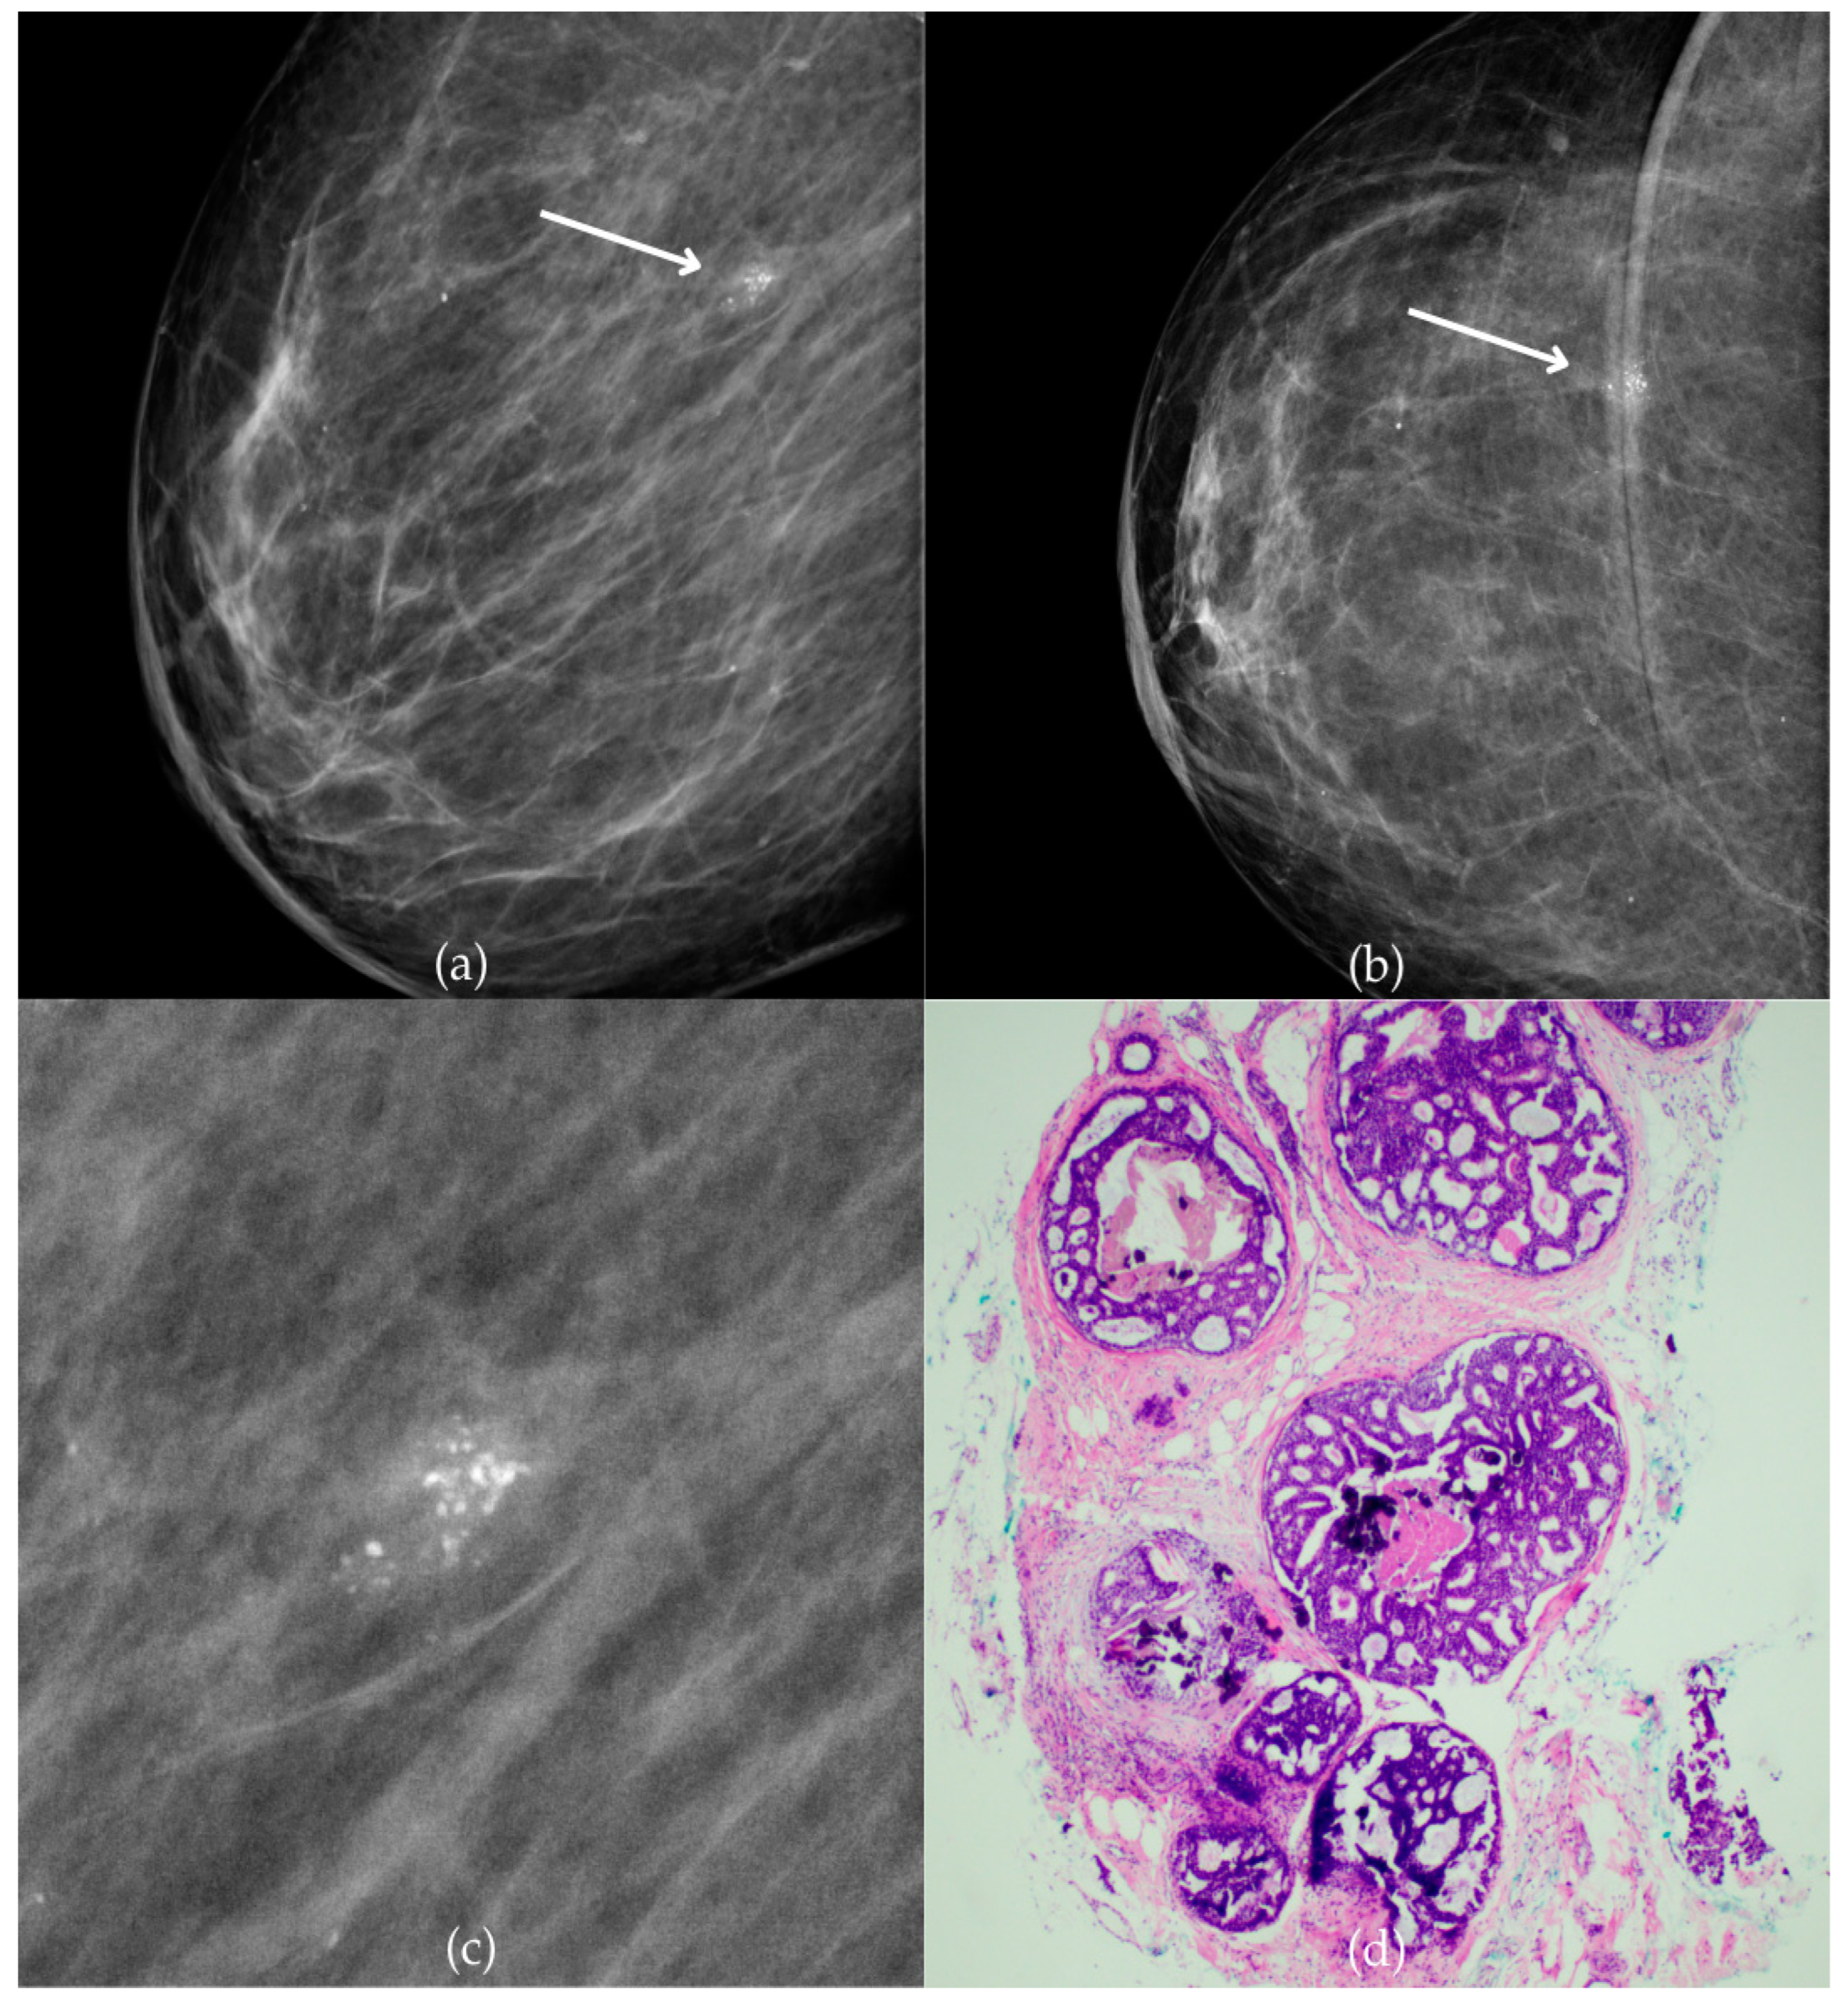

Figure 1 presents mammographic and histopathological images of a 74-year-old patient. The mammogram of the right breast shows grouped coarse heterogeneous and fine pleomorphic calcifications in the upper outer quadrant, classified as a BI-RADS 4 finding. Given the suspicious nature of these findings, a biopsy was performed. A tissue analysis confirmed the presence of a DCIS (category B5a). The patient underwent quadrantectomy, and the postoperative pathology confirmed the diagnosis. At the most recent follow-up, conducted one year after the initial diagnosis, the US examination was classified as BI-RADS 2, indicating benign findings.

Ductal carcinoma in situ (DCIS). (a) Mediolateral oblique (MLO) mammography view; (b) craniocaudal (CC) mammography view of the right breast showing grouped coarse heterogeneous and fine pleomorphic calcifications (marked with arrows) in the upper outer quadrant. (c) Magnified mammographic image of grouped coarse heterogeneous and fine pleomorphic calcifications. (d) The histopathological image of the biopsy sample reveals the characteristic features of DCIS (HE staining; 40× magnification).